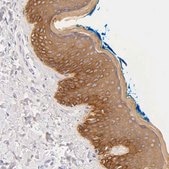

Anti-KRT17 antibody produced in rabbit

immunohistochemistry: 1:200-1:500

All Prestige Antibodies Powered by Atlas Antibodies are developed and validated by the Human Protein Atlas (HPA) project and as a result, are supported by the most extensive characterization in the industry.

The Human Protein Atlas project can be subdivided into three efforts: Human Tissue Atlas, Cancer Atlas, and Human Cell Atlas. The antibodies that have been generated in support of the Tissue and Cancer Atlas projects have been tested by immunohistochemistry against hundreds of normal and disease tissues and through the recent efforts of the Human Cell Atlas project, many have been characterized by immunofluorescence to map the human proteome not only at the tissue level but now at the subcellular level. These images and the collection of this vast data set can be viewed on the Human Protein Atlas (HPA) site by clicking on the Image Gallery link. We also provide Prestige Antibodies® protocols and other useful information.

Prestige Antibodies® are highly characterized and extensively validated antibodies with the added benefit of all available characterization data for each target being accessible via the Human Protein Atlas portal linked just below the product name at the top of this page. The uniqueness and low cross-reactivity of the Prestige Antibodies® to other proteins are due to a thorough selection of antigen regions, affinity purification, and stringent selection. Prestige antigen controls are available for every corresponding Prestige Antibody and can be found in the linkage section.

• IHC tissue array of 44 normal human tissues and 20 of the most common cancer type tissues.

Keratin 17, type I recombinant protein epitope signature tag (PrEST).